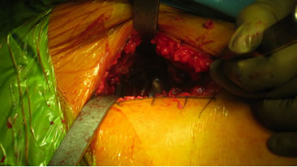

Our last ENEWS-Update January 6, 2010 highlighted Dr. Ed McPherson in evaluating Tissue Sparing Hip Techniques using a small posterior approach. This edition will highlight a single incision anterior approach performed by Dr. Bradley Walter.

Dr. Walter has been interested in tissue sparing approaches for THA and has been using the single anterior approach and short cementless stems for the past few years.

| No special table or instruments are required if a short stem is used. |

Excellent exposure of the acetabulum even with a high neck osteotomy. |

| High neck cut |

| Supine position provides good orientation for the socket preparation and insertion. |

Good exposure of the proximal femur. |